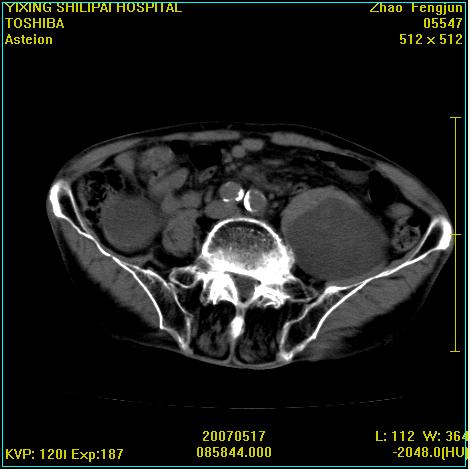

考虑:1、左侧腰大肌囊实性占位性病变(囊性神经根鞘瘤?);

2、右侧兰尾区囊性占位性病变(兰尾囊肿?囊腺癌?类癌?)

以下是引用xiaoniu在2007-5-26 10:45:00的发言:[br]腰大肌的病变应该没有问题,增强扫描还有轻度强化及细小血管影入内,应该排除脓肿,考虑占位性病变,腰大肌的占位多考虑:神经源性肿瘤。另外腹主动脉下端有真假腔的强化,考虑:主动脉夹层。[br][br][本贴已被 xiaoniu 于 2007-5-26 10:46:39 修改过]

以下是引用老爱克斯新网客在2007-5-26 18:26:00的发言:[br]1左下腹囊实性占位肿块,增强后不均匀强化,位于脊柱旁,椎体骨质无破坏软组织无肿胀,考虑神经源肿瘤神经鞘瘤可能大,2右下腹囊性占位性病变,增强后囊壁强化,考虑阑尾囊肿或囊腺瘤,